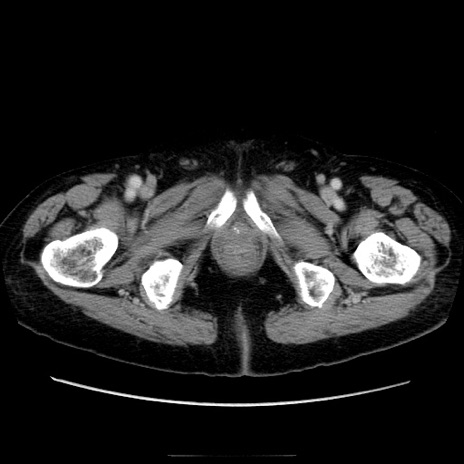

症例21(横断像)

【症例】70歳代男性

【主訴】腹痛

【現病歴】肝硬変・肝細胞癌にてかかりつけの方。約9時間前に食後より腹痛出現。症状が徐々に増悪し、嘔吐出現したため来院。

【既往歴】肝硬変、肝細胞癌(RFA、TACE後)

【身体所見】意識清明、表情苦悶様、BT 36℃、BP 129/78mmHg、P 88bpm、SpO2 97%(RA)、右上腹部から心窩部にかけて圧痛あり、反跳痛なし、筋性防御あり。

【データ】WBC 5800、CRP 0.16